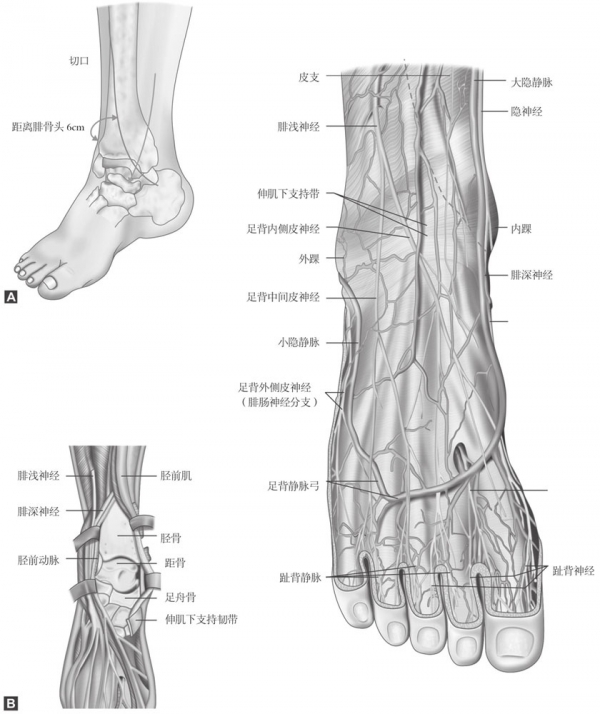

腓骨的重建利于对胫骨侧方的关键碎片进行复位。胫骨的远端通过一道位于前内侧的、覆盖胫骨远端的和位于胫骨前缘稍外侧的、沿着胫骨前肌肌腱的切口而暴露。在有骨折向后移位的患者,也可选择后外侧入路。在这些案例中,腓骨的修复都是通过相同的入路。切口止于内踝下方。注意保护腓浅和隐神经(图6)。

图6 A和B胫骨远端前内侧入路。腓浅神经和隐神经应保持完好,可能的话,也应保留隐静脉。不要为了保护血管解剖组织层太多